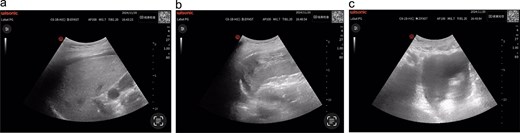

Following supine repositioning, the patient developed hypotension (74/38 mmHg) that transiently responded to phenylephrine bolus and 500 mL colloid infusion, with blood pressure stabilizing at 109/69 mmHg prior to transfer to the post-anesthesia care unit (PACU). However, within 5 min of PACU arrival, profound hemodynamic collapse occurred (56/33 mmHg, HR 94 bpm) refractory to repeated norepinephrine administration. Immediate arterial blood gas analysis revealed metabolic acidosis (pH 7.299, base excess −6.4 mmol/L) concurrent with acute anemia (Hb 77 g/L). Emergency E-FAST subsequently identified splenic capsular discontinuity and significant hemoperitoneum (Fig. 1), confirmed by ultrasound-guided aspiration of non-clotting blood. Hemoglobin levels progressively declined to a nadir of 57 g/L during this critical phase.

(a) Hepatic ultrasonography demonstrates an intact hepatic capsule with adjacent anechoic fluid collections; (b) splenic imaging reveals discontinuous capsular contour at the diaphragmatic surface with heterogeneous parenchymal echotexture; (c) pelvic cavity shows significant anechoic fluid accumulation.